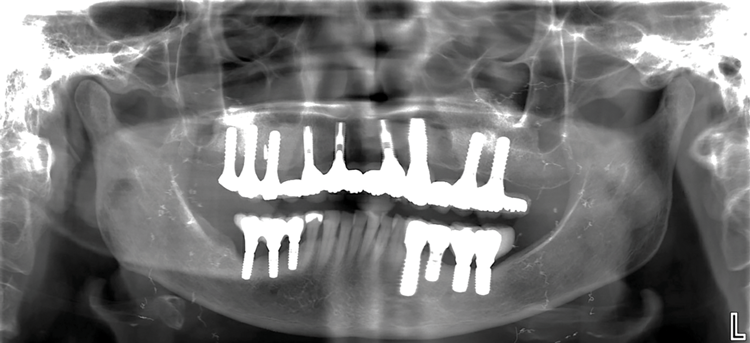

Fig 2. Initial panoramic radiograph.

Figure 2

Fig 7. Panoramic radiograph after placement of TIs and bilateral sinus augmentation with provisional prosthesis.

Figure 7

Fig 16. Panoramic radiograph at 1-year follow-up.

Figure 16

Fig 17. Panoramic radiograph at 5-year follow-up

Figure 17

Fig 18. Panoramic radiograph at 20-year follow-up.

Figure 18